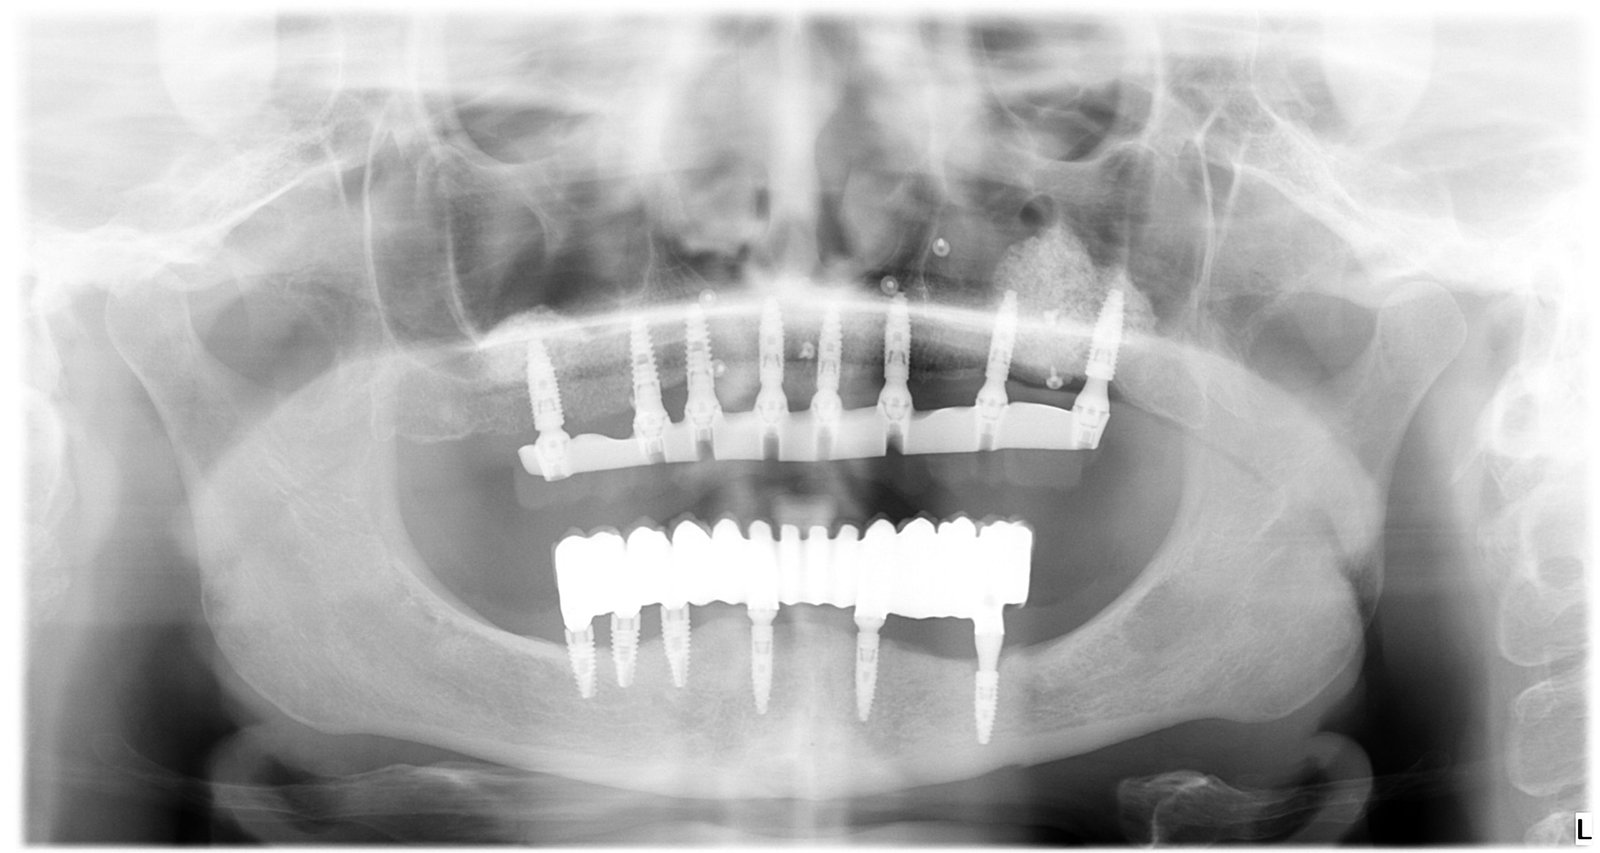

Caso 2 - caso de Implantes dentales

El paciente presentaba pérdidas dentales que comprometían tanto la función como la estabilidad de su mordida. Mediante un tratamiento con implantes personalizados logramos restablecer una dentadura fija, estable y adaptada a su anatomía.

Se observa la colocación de los implantes en la posición óptima, garantizando una base sólida para la posterior rehabilitación protésica.

La radiografía final confirma la correcta integración de los implantes, asegurando una solución duradera y completamente funcional.